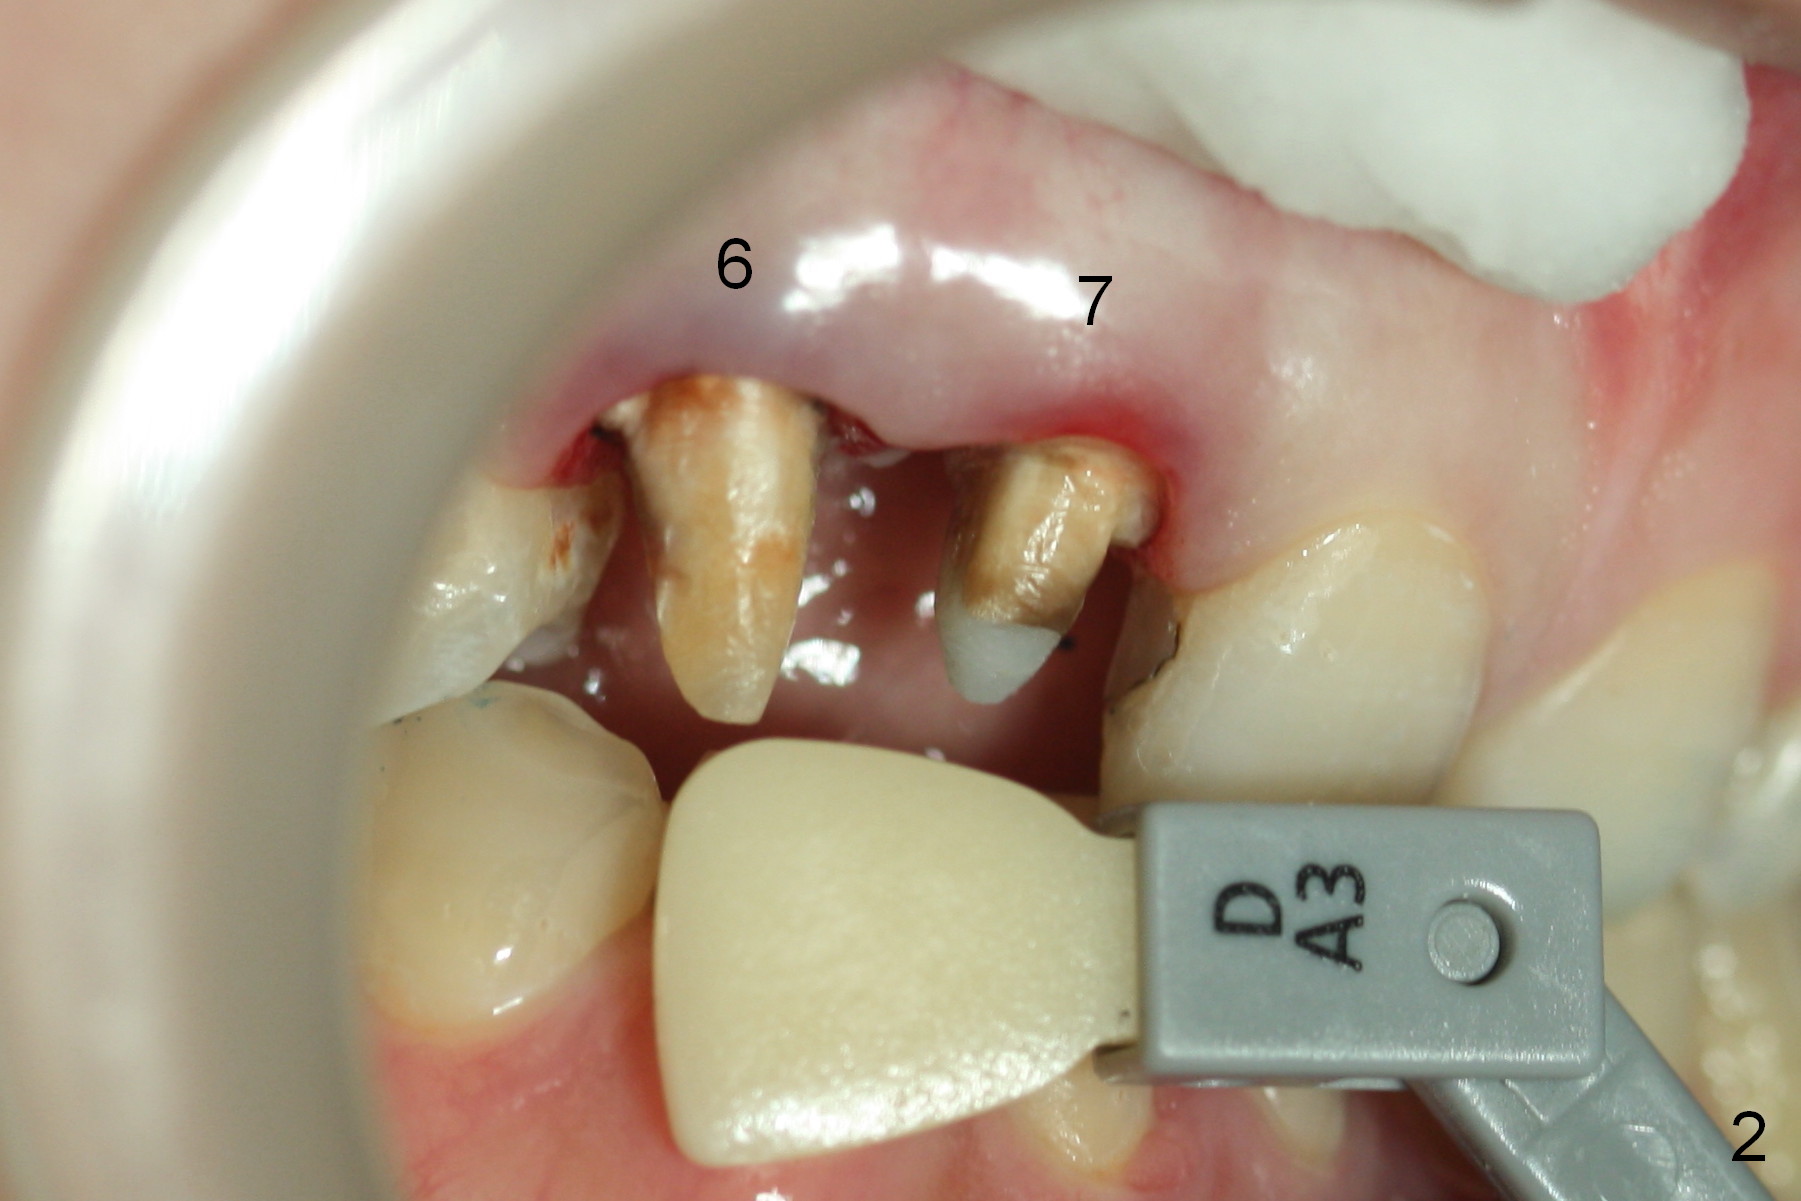

A 30-year-old lady has finished #7 RCT retreat and prefabricated post & core (Fig.1,2). Emax is chosen if it can cover the brownish discoloraton.